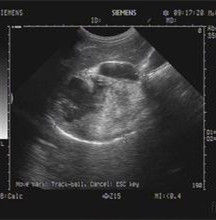

肝腎隱窩,為仰臥位時腹腔的最低處,是腹膜腔內液體易積聚之處。

肝腎隱窩,是在肝右葉髒面和右腎及結腸肝曲之間,稱肝腎隱窩。